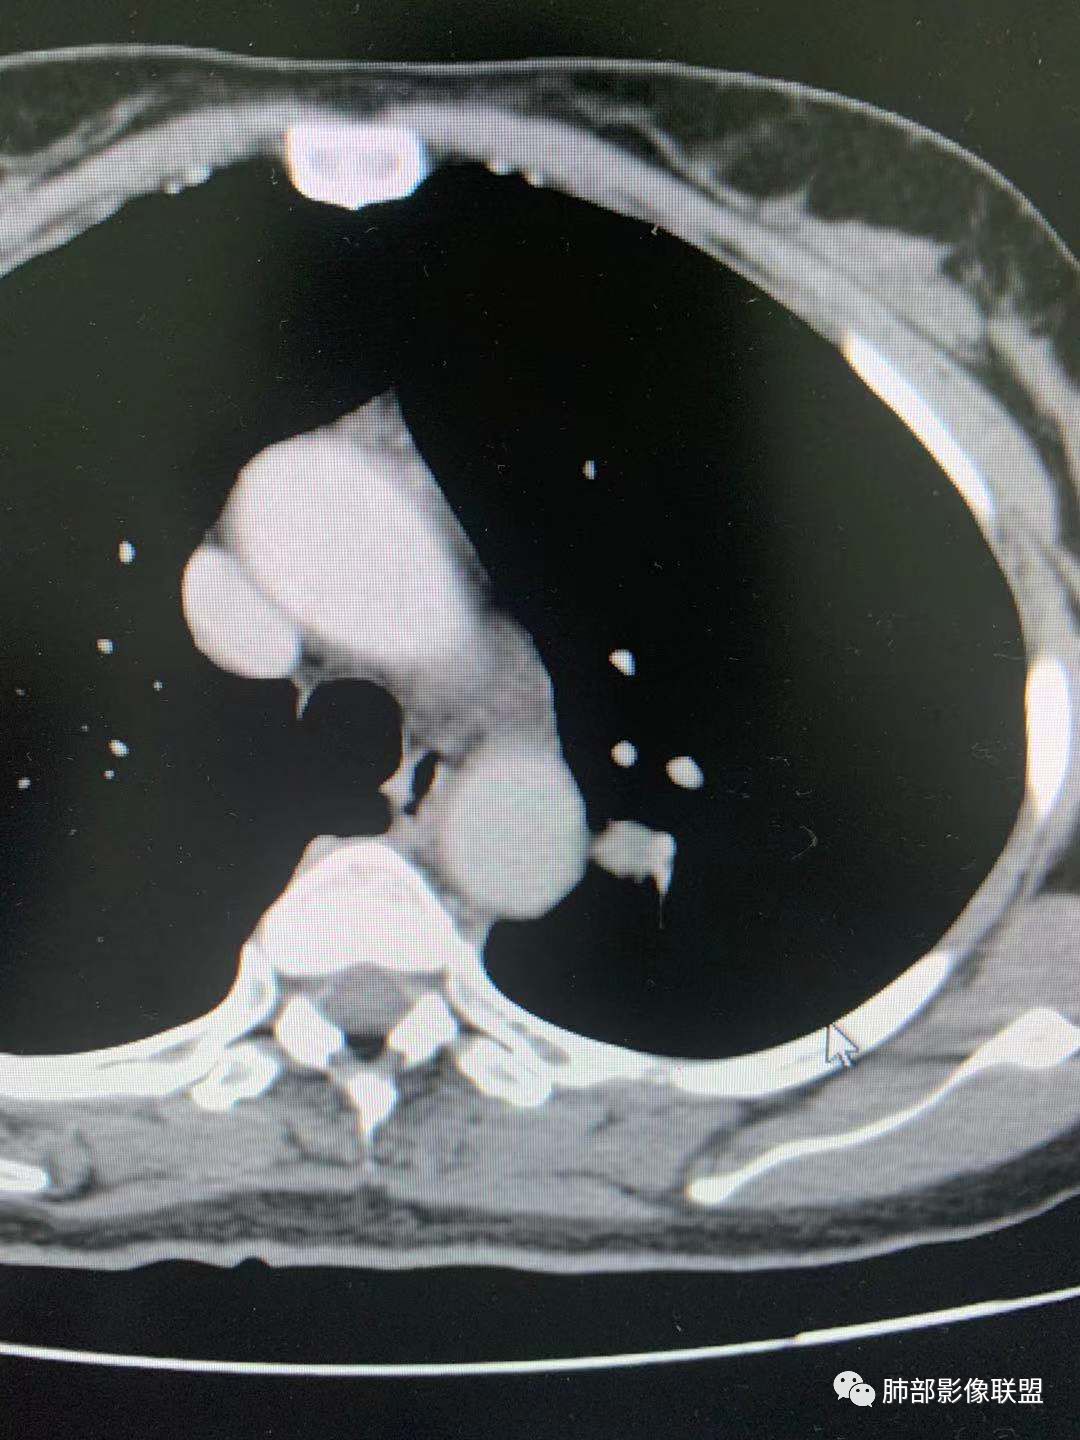

一.尖后段高密度大结节:

1.左肺上叶尖后段较大类圆形实性密度结节影,密度均匀,中等程度强化。

2.实性密度区边缘相当清楚,表面欠光整,偶见毛刺、棘突和旁出血管结构,未见典型的深分叶及邻近胸膜凹陷。

3.可疑支气管进入受阻。可惜缺乏连贯图像或冠矢状位以资判断。

4.病灶与胸膜之间有连线,邻近段支气管及肺血管整体后移,提示病灶还是有一定收缩性。

如上,单就这实性结节,硬化性肺细胞瘤(PSP)和腺癌似乎都能够解释,形态太规整了一些。

5.病灶周围见边界清楚的磨玻璃影,有点醒目,有点意外!

这是无论如何不能忽视的征象!

这点强烈提示,要么整个病灶恶性(腺癌),要么良性病灶旁滋生恶性病灶。

两年前左上肺的病灶什么位置,什么模样,是否相关?我们不得而知。